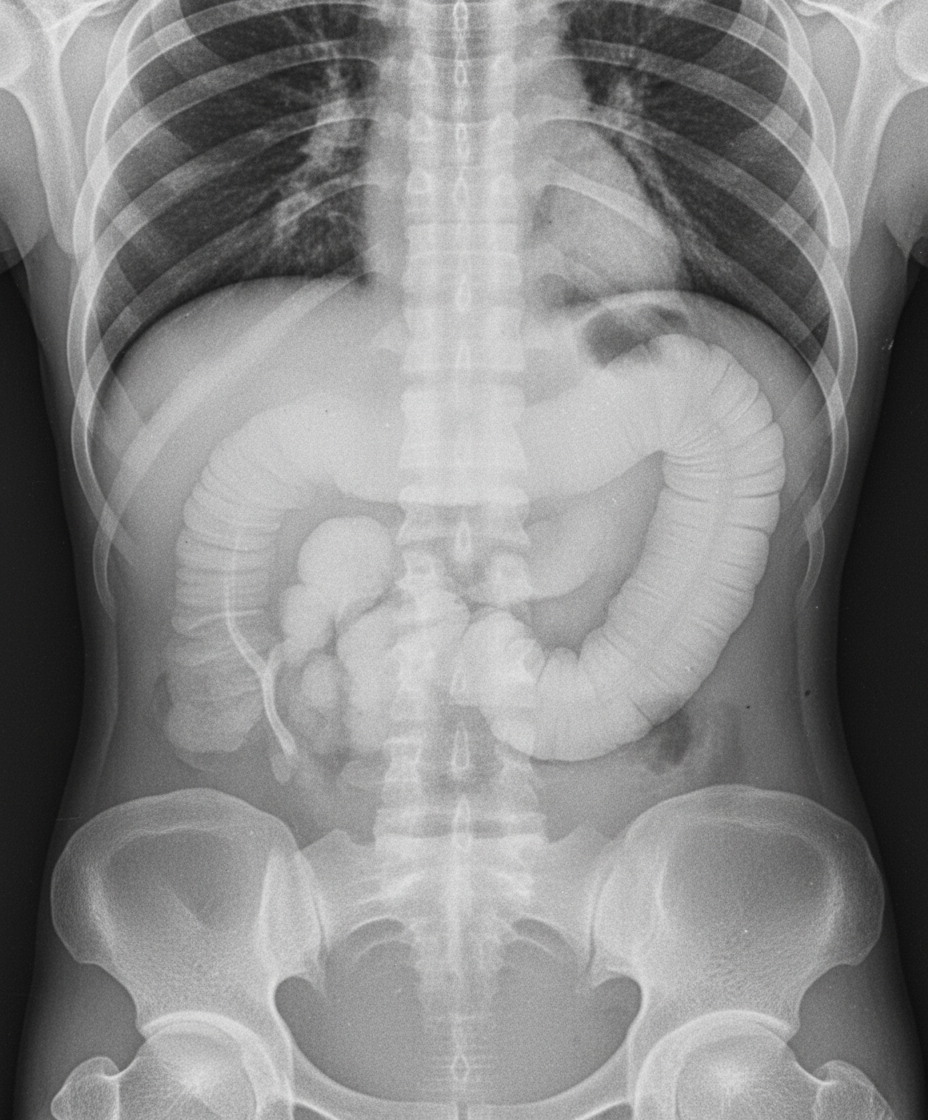

A middle-aged male, a diagnosed case of chronic ulcerative colitis, presents to the emergency department with fever and diarrhea for one week, and acute onset abdominal pain for six hours. An erect abdominal X-ray was taken as shown. What is the likely diagnosis?

Explanation: ***Toxic megacolon*** - A patient with **chronic ulcerative colitis** presenting with fever, diarrhea, and acute abdominal pain strongly suggests **toxic megacolon**, a life-threatening complication. - The erect abdominal X-ray would show **colonic dilatation >6 cm** with **loss of haustral markings**, pathognomonic features of this condition. *Pseudomembranous colitis* - Typically caused by **Clostridioides difficile** infection, often following antibiotic therapy, which is not mentioned in this case. - While it can cause fever and diarrhea, it rarely presents with the **severe colonic dilatation** seen on imaging in toxic megacolon. *Adenocarcinoma of the colon* - Usually presents with **gradual onset** symptoms like weight loss, changes in bowel habits, and occult bleeding over months. - Would not cause the **acute severe dilatation** and systemic toxicity seen in this emergency presentation. *Pneumatosis intestinalis* - Characterized by **gas within the bowel wall** creating a linear lucency pattern on X-ray, not colonic dilatation. - Typically associated with **ischemic bowel disease** or severe inflammation, but doesn't match the clinical presentation of toxic megacolon.